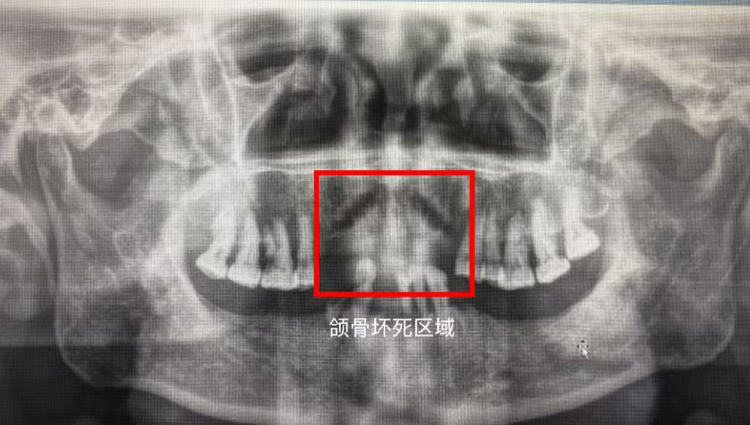

“可以去重医附二院整形与颌面外科看看。”医生的建议为王先生指明了方向,他立即向该科夏德林主任团队求助。结合双膦酸盐、地舒单抗等用药史,药物相关性颌骨坏死的诊断结果让王先生一脸茫然。

由于上颌骨坏死、骨髓炎病情严重,夏德林主任团队联合口腔科、肿瘤科等多学科,兼顾疾病治疗与功能保全,精准制定手术、药物等综合管理方案,奋力帮他解除痛苦。

药物相关性颌骨坏死,是指骨质疏松和多发性骨髓瘤、乳腺癌、前列腺癌、肺癌等恶性肿瘤骨转移等患者,因使用双膦酸盐、地舒单抗等药物所致的颌骨坏死类疾病。“虽然这些药物有致颌骨坏死风险,但也能有效治疗骨质疏松及肿瘤骨转移,患者不能因噎废食,拒绝用药。”整形与颌面外科鲜红春医师指出,口腔科、肿瘤科、颌面外科应联合采用多学科协作诊疗模式及早期规范化干预,做好用药前全面口腔评估、治疗期风险规避和长期维护计划。